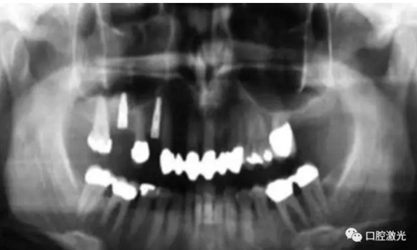

#33,#43顯示存在種植體周圍炎

氣化切除種植體周圍的軟組織可以獲得一個干凈的種植體表面以及去除感染的生物組織層。其目的是穩(wěn)定種植體周圍的組織結(jié)構(gòu),從而避免骨的缺失導致種植體的失敗。但由于種植體的數(shù)量逐步增加以及患者年齡的逐漸增大,出現(xiàn)種植體周圍炎的概率會顯著提高??谇患す獐煼ǖ某霈F(xiàn),擴大了種植體周圍炎的治療范圍并提供了維持健康的種植體的一種全新方法。